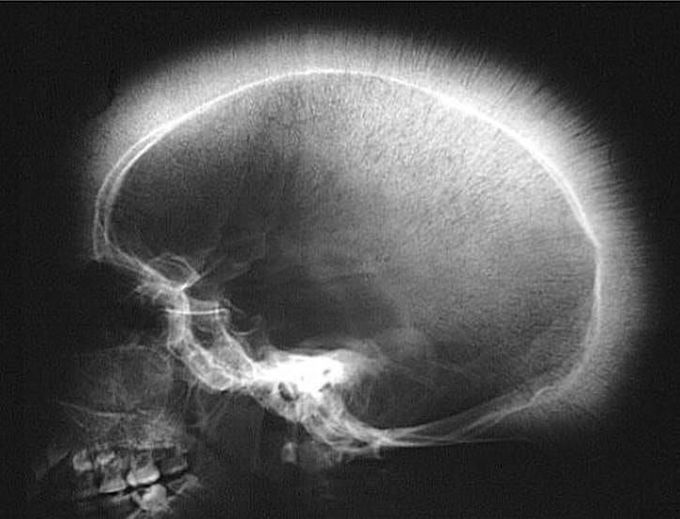

This patient has jaundice and anemia. whats your diagnosis? @medicalcortex

Thalasemia, clinical features in the skull x ray named crew cut/hair on end apperance, to diagnose thalasemia Beta Major/alpha would like to examine HbF & HbA2

Crew cut appearance due to expansion. Seen in thalassemia major